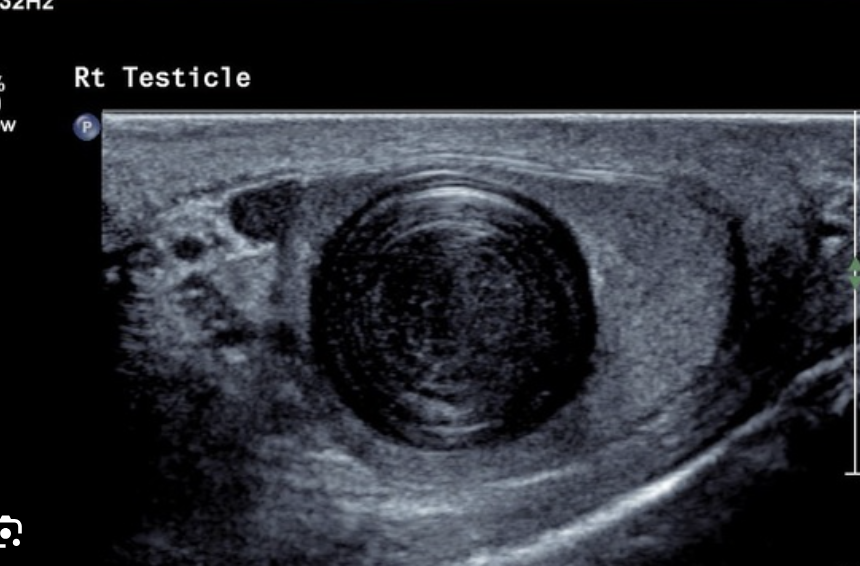

What are the sonographic findings of epididymitis?

Enlarged, hypoechoic epididymis with increased blood flow (hyperemia).

What are the sonographic findings when infection extends into the testicle (orchitis)?

Enlarged, hypoechoic, and hyperemic testicle with reactive hydrocele.